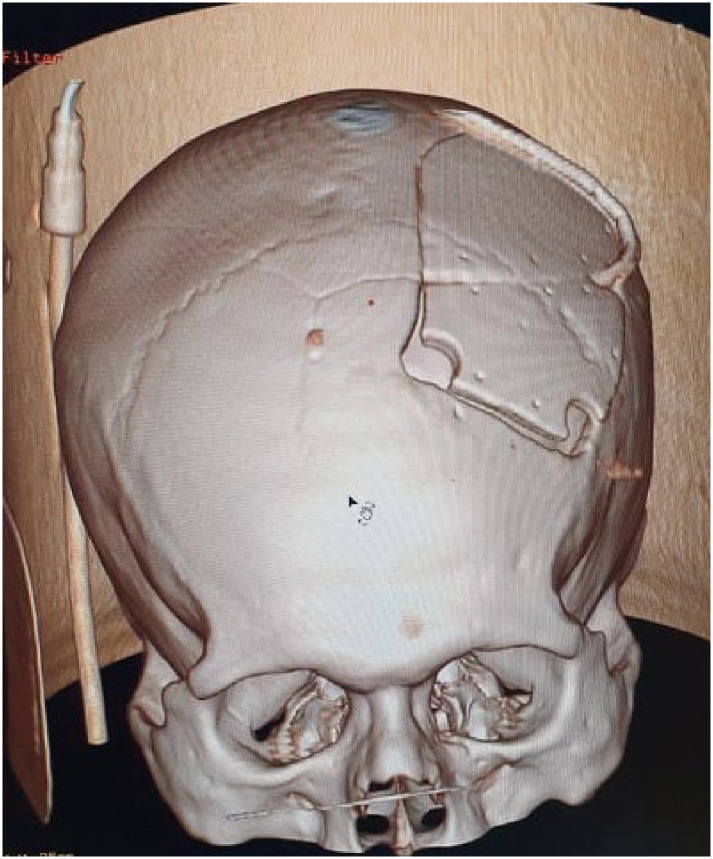

Vertex epidural hematomas are very uncommon complications of traumatic head injury. Besides the volume of the epidural bleeding, compression of the superior sagittal sinus may be source for added elevated intracranial pressure. Clinical presentation of such lesions is heterogenous and symptoms can develop in an acute to a chronic frame. Radiological diagnosis can sometimes be challenging. Due to its rarity, such lesions have been only reported on case reports and small series and the management remain controversial. Hereby we report 3 cases of surgically managed post traumatic acute epidural hematomas of the vertex. Wen also went through a literature-based discussion of clinical, radiological and therapeutic features related to this condition.

Abstract Image